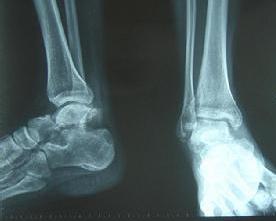

♥距骨后外结节骨折

距骨后外结节骨折是跖屈损伤的结果,压力从胫骨后下唇作用于距骨结节。这个软骨接合部骨折的发生,通常是在运动时突然以跖骨或脚趾起跳的后果。芭蕾舞演员的距骨外侧结节伸长(Stieda突)更易于发生这种损伤。